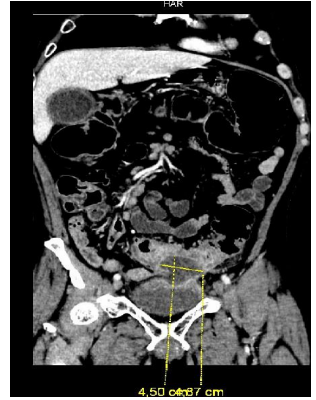

The initial blood analysis revealed a leukocytosis of 15,000/µL (4,000-11,000/µL) with neutrophilia and C-reactive protein (CRP) of 245 mg/L (0-0.5 mg/L), as well as anemia with a profile of chronic disorders. The abdominal x-ray showed abundant gas without signs of intestinal obstruction. An abdominopelvic CT with intravenous contrast was performed (Figure. 1, 2 and 3) in which radiological data compatible with a new episode of diverticulitis were observed, as well as an abscess on the lower surface of the sigmoid.

Figure 2: Coronal section of abdominopelvic CT, with abscess measuring 4.5 x 4.87 cm